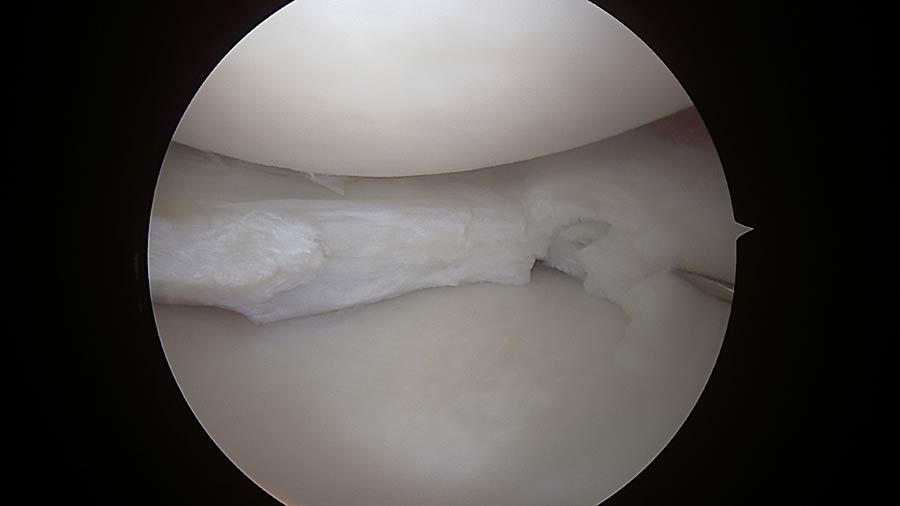

Lesioni meniscali: I menischi svolgono un ruolo essenziale nella protezione dell’articolazione. Una loro lesione può provocare dolore improvviso, blocchi articolari e limitazione funzionale. Attraverso procedure artroscopiche mini-invasive intervengo in modo preciso sulla parte danneggiata, riducendo i tempi di recupero e facilitando il ritorno alle normali attività quotidiane.